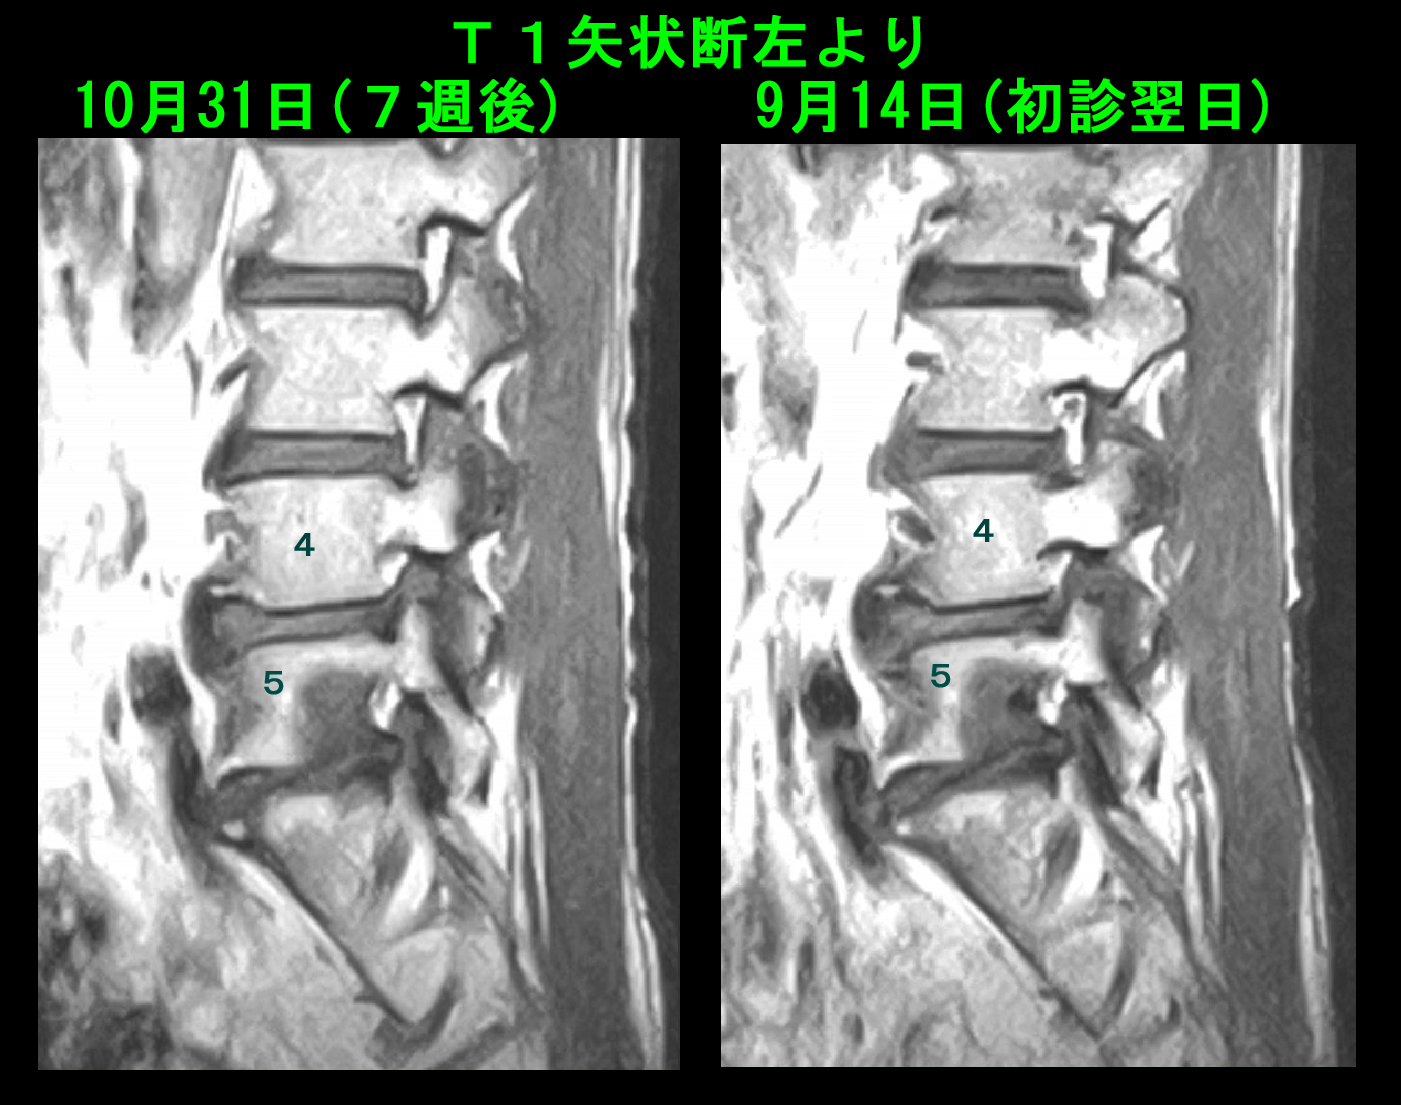

10月31日(7週後)にMRI再検査を行っています。T1の画像で変化を提示します。

L4の前方下部の右よりの黒かった骨損傷所見は正常に近い状態に改善しています。

71才男 MR5.jpg

左よりのL5後方下部の骨損傷所見はあまり改善の所見がえられていませんが、中心部の濃い黒い所見は軽減しています。